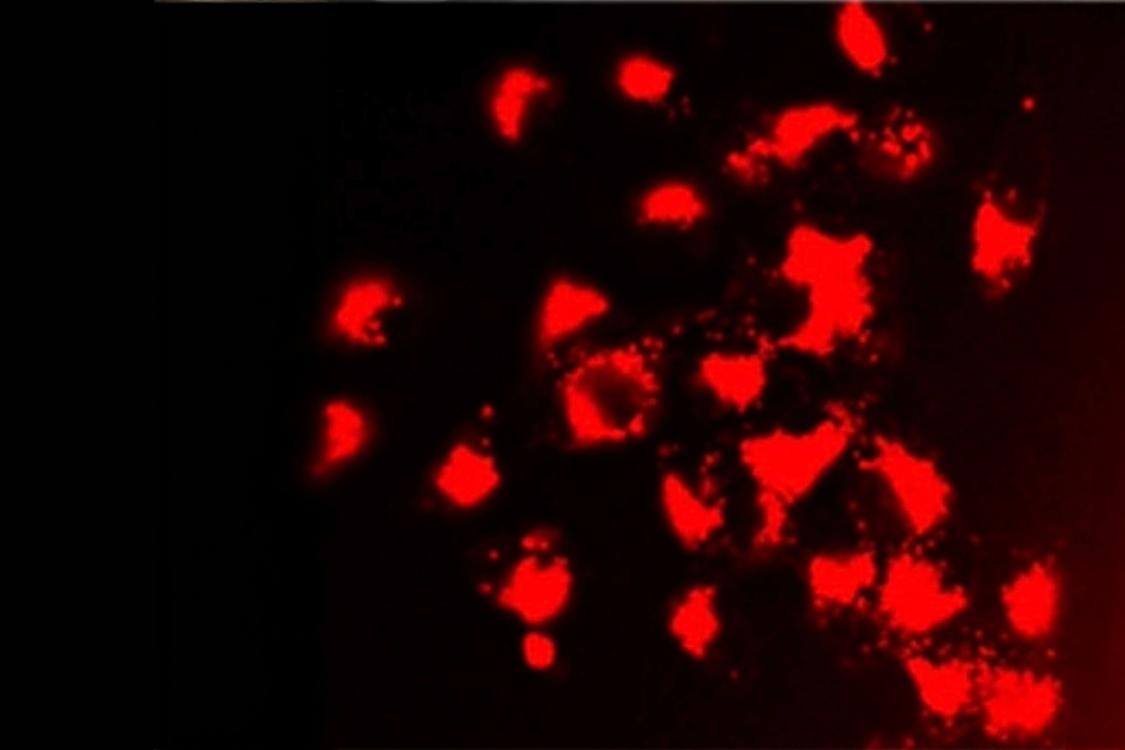

Sparkling results in nanoscience

New research from Queen’s Carbon to Metal Coating Institute could lead to the use of tiny structures of gold to deliver precise cancer treatment.